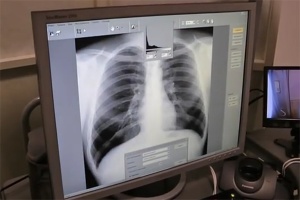

Умершая от открытой формы туберкулеза медсестра зеленоградской школы №1151 не делала флюорографию 5 лет, а поддельные справки ей выдавала знакомая в Бежецкой ЦРБ.

Медсестра зеленоградской школы №1151, скончавшаяся от открытой формы туберкулеза, могла получать поддельные справки об успешном прохождении флюорографии через своих знакомых в больнице Тверской области.

При поступлении в больницу заболевшая скрыла свое место работы, из-за чего дезинфекция в зданиях школы и детского сада была проведена только спустя несколько недель.